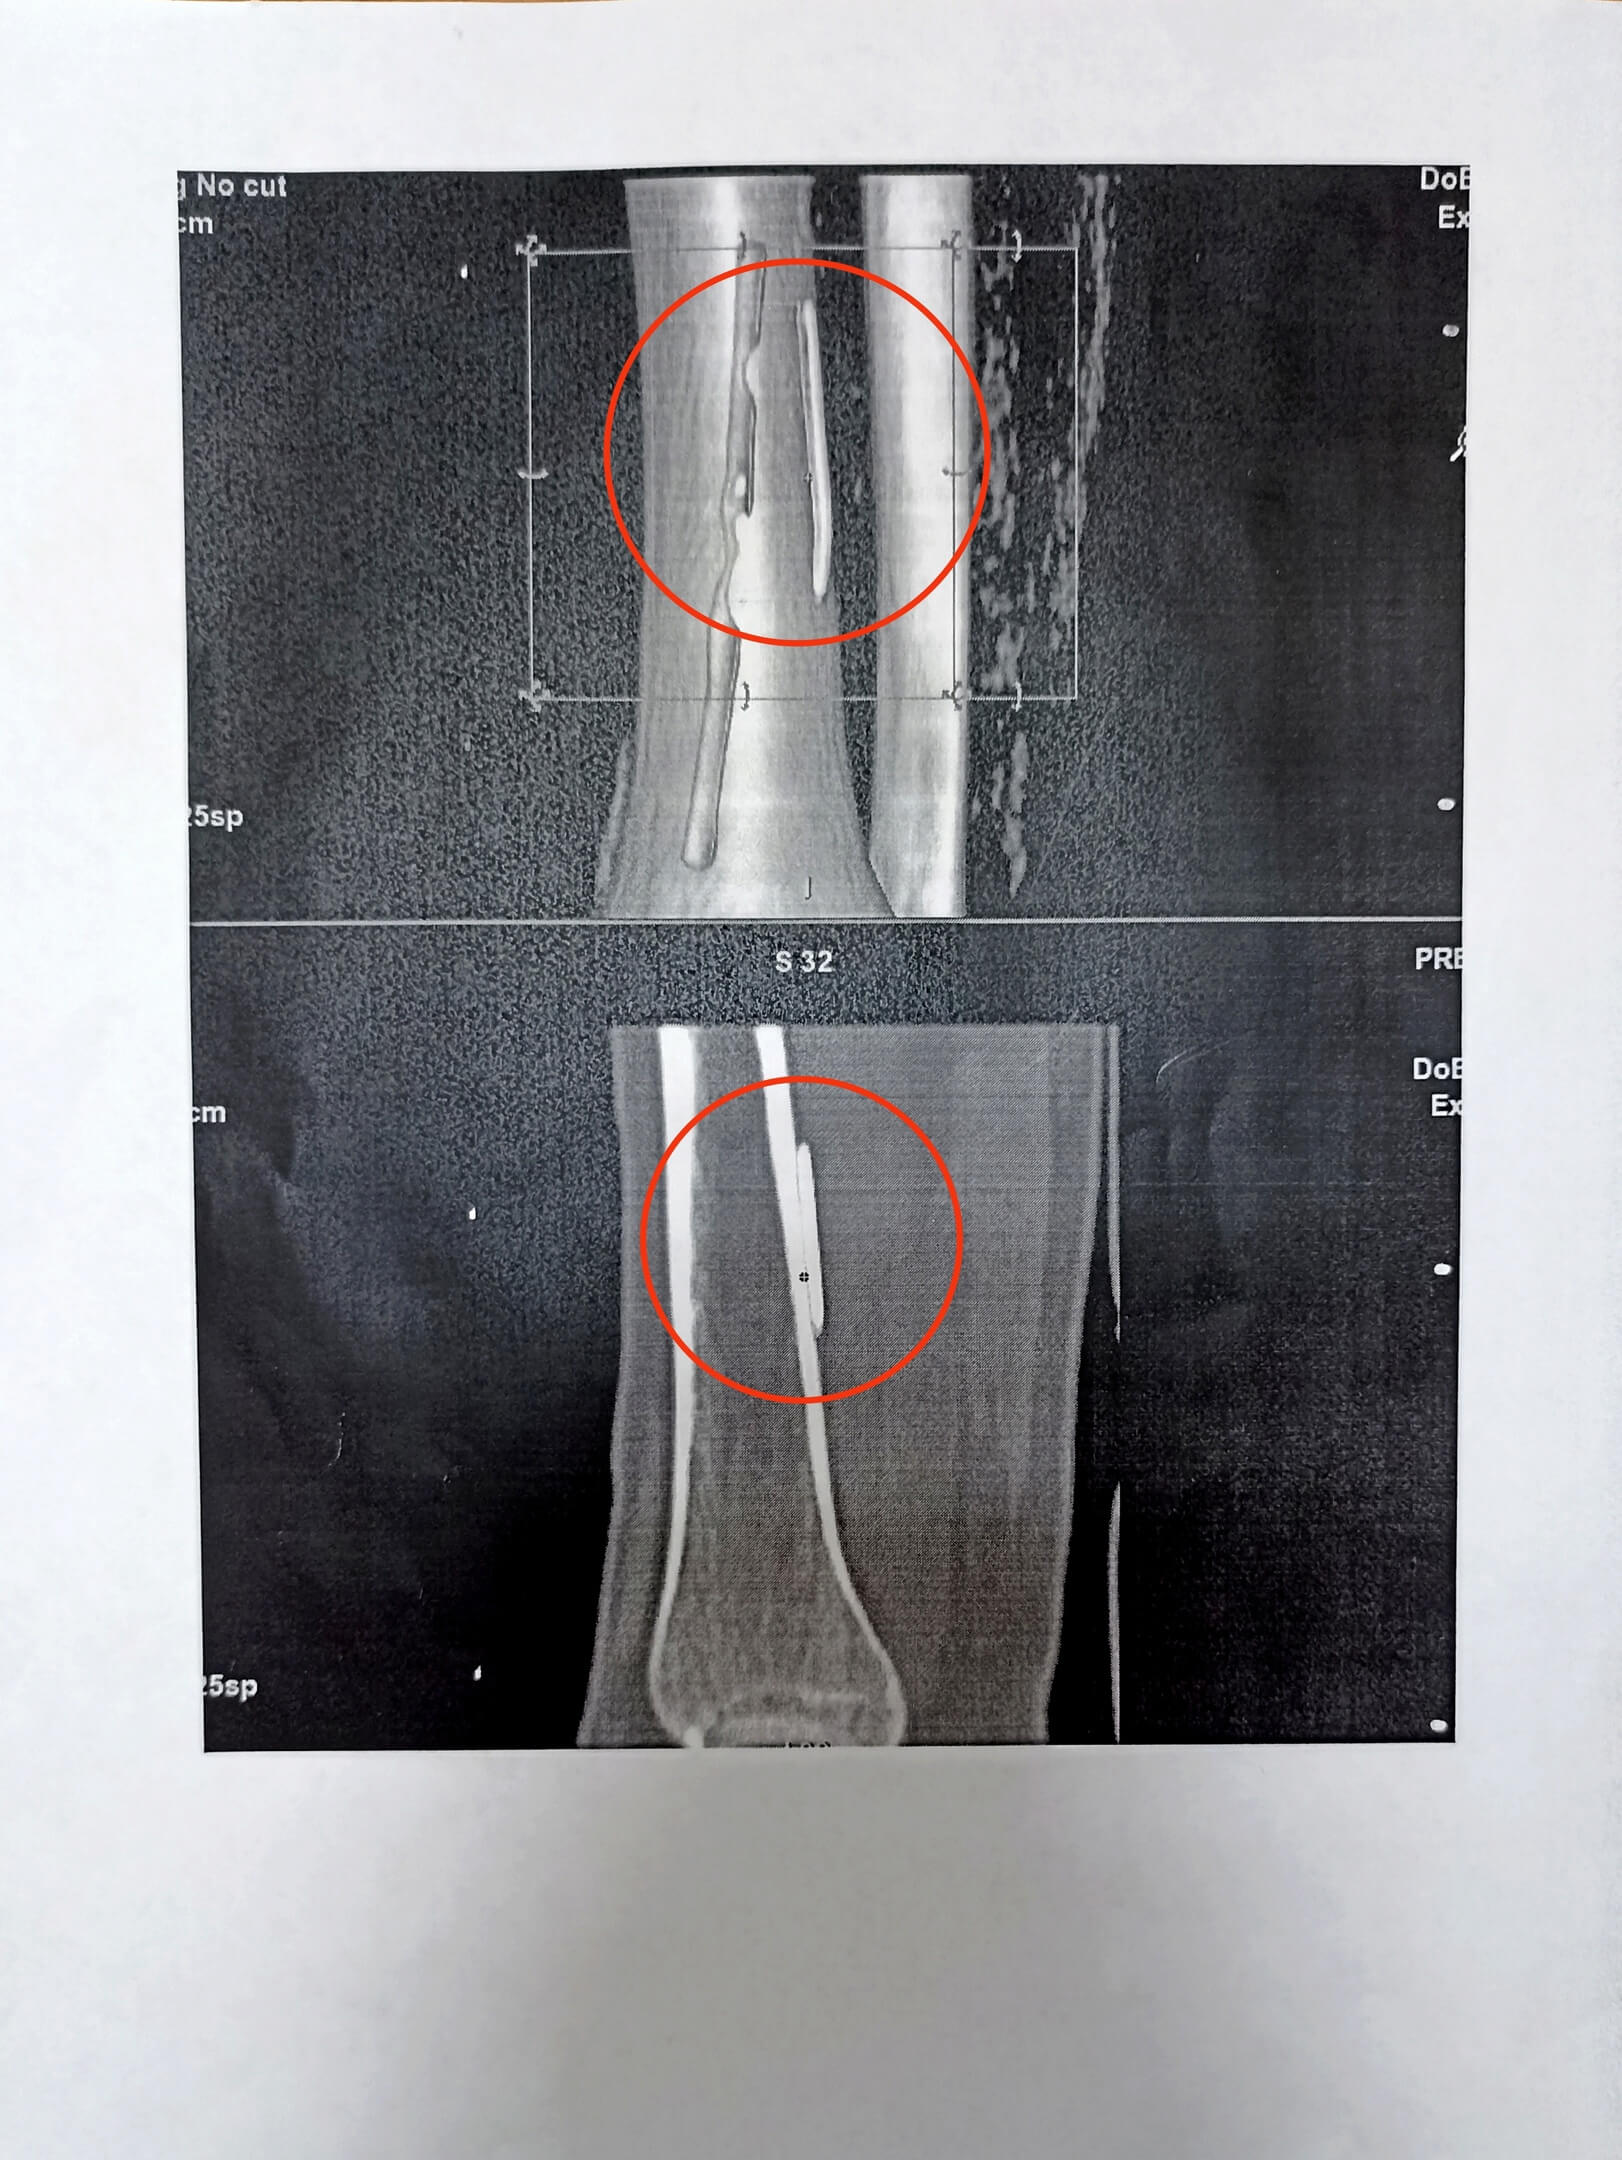

Скорая помощь привезла пациентку в травмпункт, где в течение часа пытались достать инородное тело. Оттуда девушку направили в ДГКБ № 7. По словам хирурга детского отделения гнойной хирургии больницы, по снимкам было сложно понять, на какой глубине находится иголка. Она оказалась под икроножной мышцей, которая, сокращаясь, продвинула иглу от уровня ахиллова сухожилия до средней трети  голени.

По словам пациентки, в первые дни боль отдавала в бедро. Хирурги провели операцию, но попытки найти инородное тело не увенчались успехом. После проведённой компьютерной томографии, которую помогли осуществить медики из Алтайского краевого центра охраны материнства и детства, выяснилось, что игла находится по задней поверхности большеберцовой  кости.

Следующая операция длилась всего 40 минут. Врачи вышли на кость, начали отслаивать мышцы и обнаружили иголку. Она находилась рядом с передней большеберцовой артерией. Если бы она повредилась во время операции, то могло бы развиться серьёзное  кровотечение.